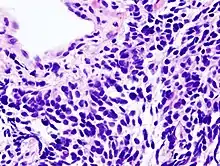

Дрібноклітинна карцинома легені

У випадку дрібноклітинної карциноми клітини містять щільні нейросекреторні гранули (везикули, що містять нейроендокринні гормони), які пов'язують пухлину з ендокринним/паранеопластичним синдромом.[50] У більшості випадків пухлини виникають у великих дихальних шляхах (первинних і вторинних бронхах).[13] Ці пухлини ростуть швидко і поширюються на ранніх стадіях захворювання. У 60-70 % випадків утворюються метастази. Цей тип раку легень в значній мірі пов'язаний з палінням.[3]